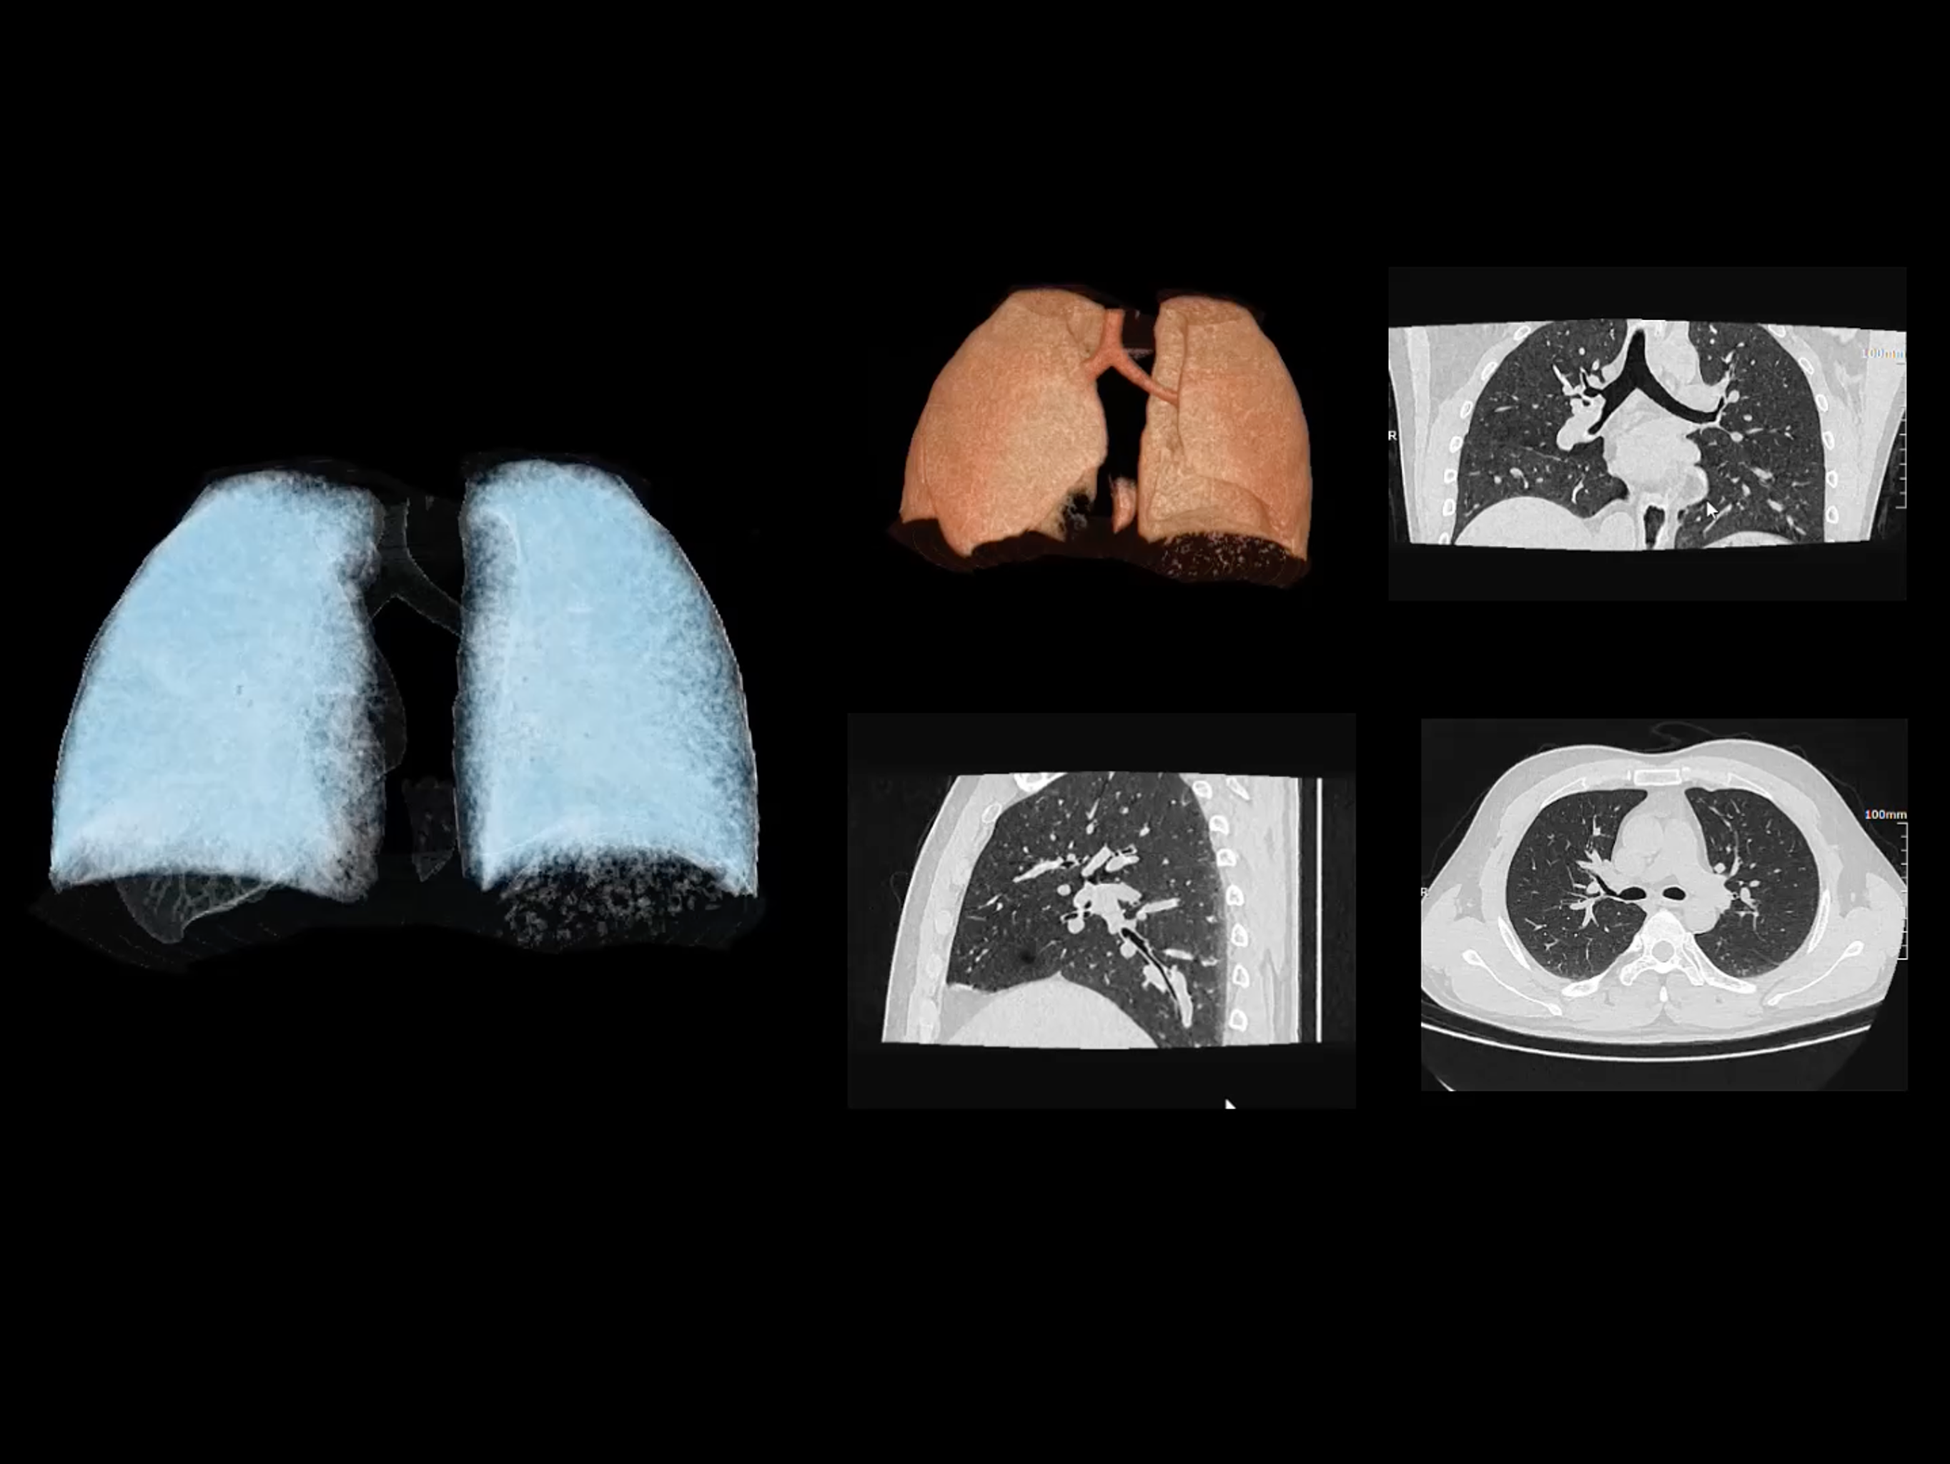

全身各部位动态CT成像

uCT SiriuX® 以全新双宽体系统架构,同步实现超高时间分辨率与宽体容积覆盖兼得,全面释放性能潜能,敏锐捕捉人体生理运动全景,带来动态影像新视角。

巅峰系统形态

双宽体“零”噪声时空探测器,Z 方向覆盖达16 cm,单圈即可完整扫描头颅、心脏等关键器官,结合超高时间分辨率,可实现真正意义上的全身各部位高清动态成像,让每一次扫描都更高效、更精准。

uCT SiriuX® 以16cm超宽Z轴覆盖,使超高时间分辨率应用于完整器官成像。无论是心脏搏动还是关节运动,整个目标区域可在同一瞬时被完整、清晰地捕捉,彻底消除时序误差,实现从“局部瞬间”到“全器官瞬时”的成像跨越。